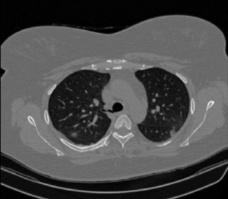

Figure 1 shows four CT scan slices, two from a non-COVID-19 CT scan, on the left and two from a COVID-19 scan, on the right. Bilateral ground glass regions are seen especially in lower lung lobes in the COVID-19 slices.